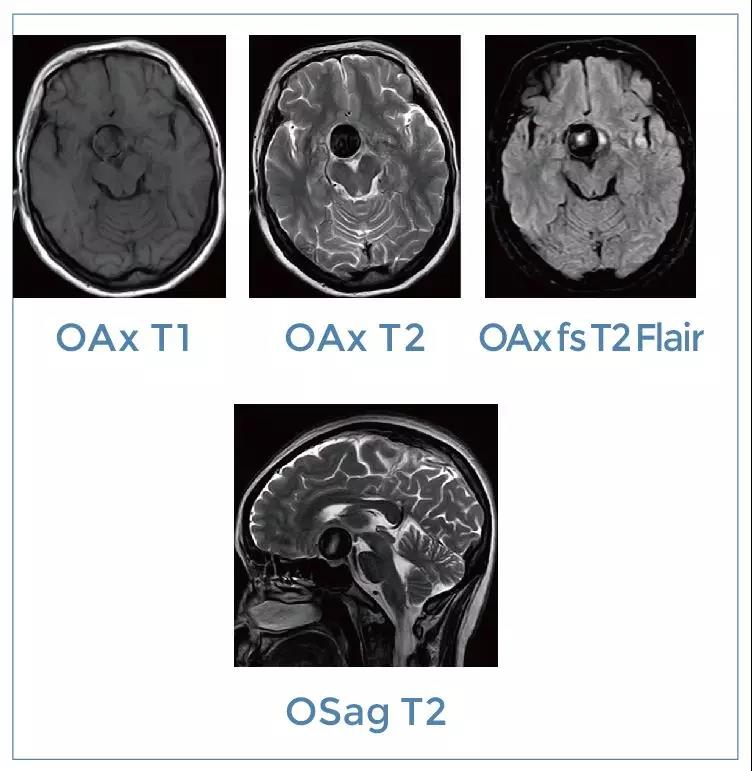

【朗润影像档案】磁共振影像病例分享(编号20191229)